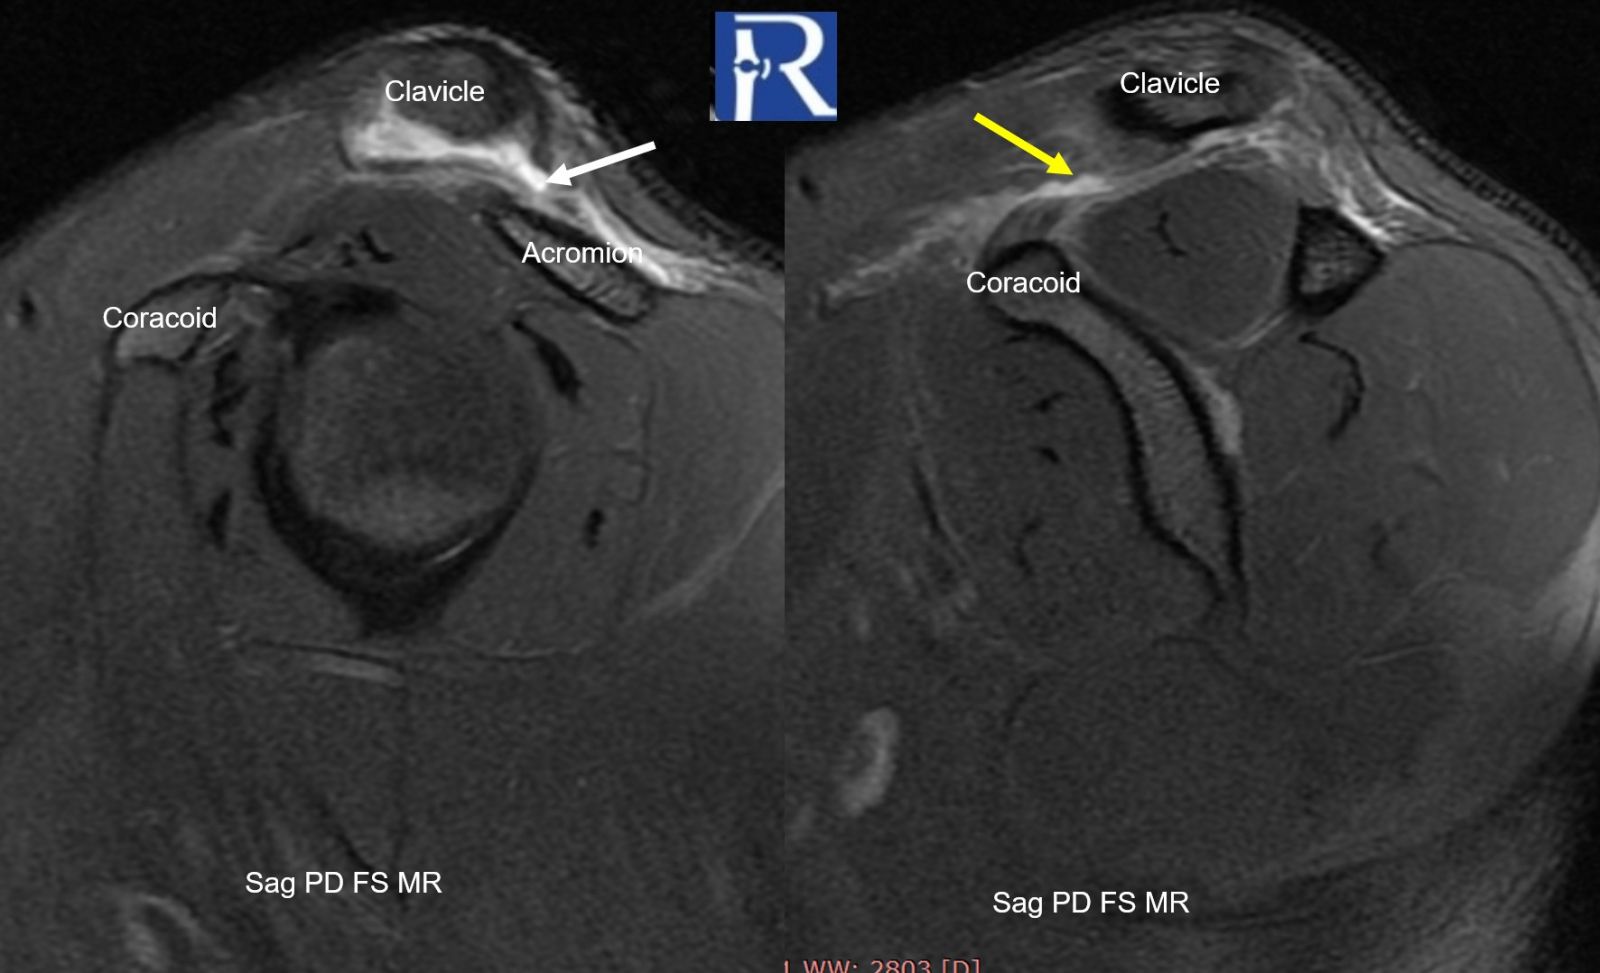

Magnetic Resonance Imaging (MRI)

- Full-thickness tear of the acromioclavicular ligament (white arrow)

- Complete disruption of the coracoclavicular ligament (yellow arrow)

- Fluid/hemorrhagic signal within the AC joint (white arrow)

- Marked periarticular edema (asterisk * optional)

- Persistent widening of the coracoclavicular distance (~20 mm) (red line)

→ MRI confirms complete ligamentous disruption consistent with Grade 3 injury

- Complete rupture of both AC and CC ligaments (yellow arrow)

- Vertical instability with clavicular elevation (white arrow)

- Complete CC ligament rupture (yellow arrow)

- Clavicle overrides acromion (white arrow)